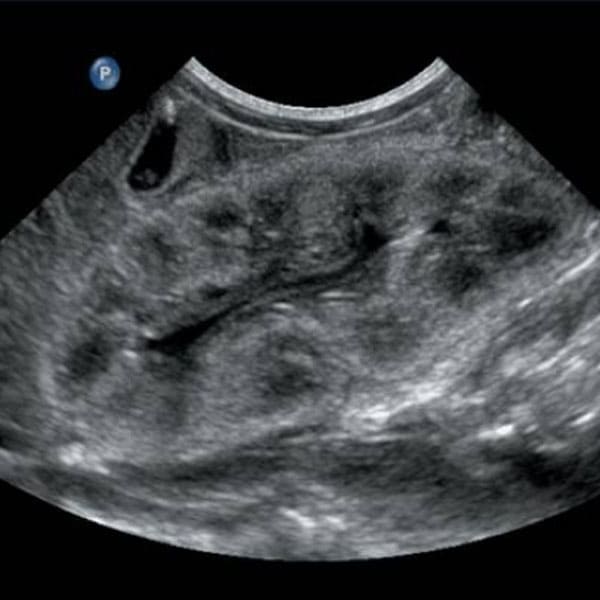

Realización de ultrasonido renal

Es un examen seguro y sin dolor el cual permite al nefrólogo ver imágenes de los riñones y la vía urinaria.